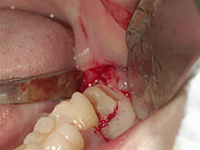

歯ぐきを切開し、親知らずの一部を削りました。

歯ぐきを戻し、縫合しました。右は削りだした親知らずです。